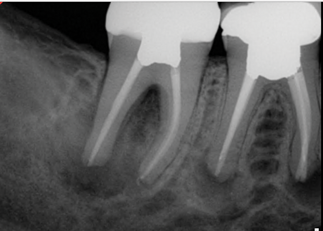

(1.) Preoperative radiograph of teeth Nos. 30 and 31 exhibiting previously treated, symptomatic apical periodontitis and pulp necrosis with a chronic apical abscess and an endodontic-periodontic lesion, respectively.

Figure 1

(2.) Postoperative radiograph after the performance of nonsurgical root canal re-treatment on tooth No. 30 and root canal therapy with hydraulic condensation and bioceramic sealer on both teeth followed by amalgam core buildups. (Case courtesy of David Tran, DMD, Advanced Graduate Program in Endodontics, Harvard School of Dental Medicine).

Figure 2